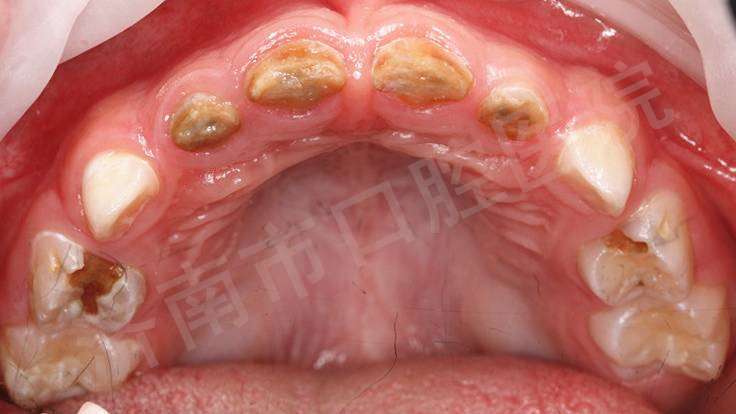

低龄儿童龋

这种同时累及前牙区多个乳牙的蛀牙,专业名称是早期(低龄)儿童龋(ecc)

喂养龋是低龄儿童龋的一种特殊类型,主要由于不良的喂养习惯所致,包括